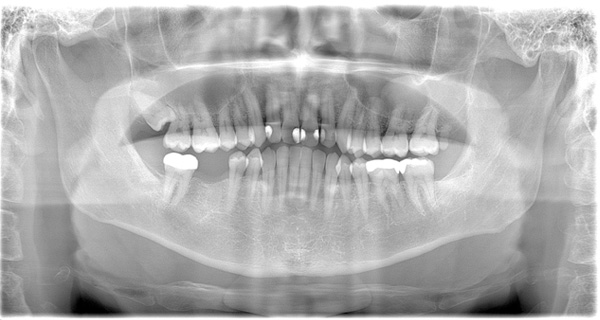

| 年代・性別 | 50代 男性 |

|---|---|

| 主訴 | 前医で前歯を抜かなければならないがインプラントはできないと言われた |

| 治療期間 | 約12ヶ月 |

| 費用 | 600,000円 |

| 治療内容 | インプラント、骨造成、結合組織移植、セラミック修復 |

| 治療に伴うリスク | インプラント周囲炎 セラミックの破折、脱離 |